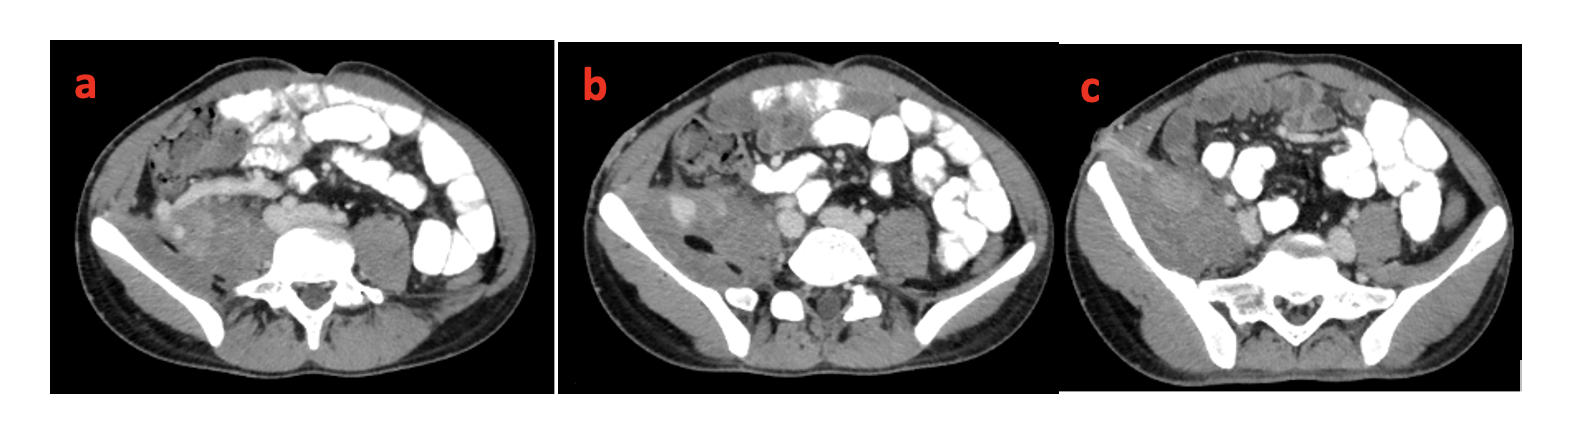

Based on the imaging findings, the patient was diagnosed as having ectopic varices in the right iliac fossa secondary to portal hypertension, which are seen communicating around the opening in the abdominal wall, causing venous congestion and nonhealing of the abdominal wall wound. It was also evident that the ileocolic branch of the superior mesenteric vein (SMV) was the afferent vein and the abdominal wall vein, predominantly the right inferior epigastric vein, was the efferent vein (Figure 4).

After a multidisciplinary meeting, percutaneous embolization of the ectopic varices was planned; however, the SMV tributary (afferent vein) was not clearly delineated on the duplex sonography. The inferior epigastric vein over the anterior abdominal was cannulated with an 18-gauge Insyte catheter (BD) using ultrasound guidance. A radiolucent plastic container was placed over the anterior abdominal wall, over the discharging sinus, and compressed using a sponge-holding forceps to prevent antegrade flow into the abdominal wall veins during contrast injection. Contrast injection and fluoroscopy showed retrograde opacification of the varices, SMV tributary, and portal vein. The tributary (afferent vein) was then localized on ultrasound and was cannulated using a 22-gauge spinal needle. Contrast injection and fluoroscopy showed antegrade flow into the varices around the abdominal wall stoma and drainage into the abdominal wall veins. Using a road map guidance, 25% glue (0.5 mL Histoacryl [B Braun] mixed with 1.5 mL ethiodized oil) was used to embolize the varices. Post-embolization contrast injection through the previously cannulated abdominal vein, after adequate compression of the abdominal wall veins, did not reveal any opacification of the varices and there was no opacification of the SMV and portal vein (Figure 5).